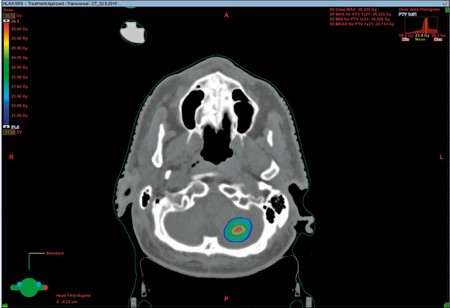

Nakonturované CT snímky přebírá radiologický fyzik k vytvoření ozařovacího plánu. V plánovacím systému se složitými výpočty vymodeluje 3D rozložení dávky. Kritéria plánu zadává plánující lékař. Hotový ozařovací plán kontroluje a schvaluje tým lékařů (obr. 10, 11).

Obr. 10 – Rozložení naplánované dávky záření v cílovém objemu